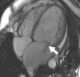

Idiopathic dilated cardiomyopathy

Dilated cardiomyopathy (DCM) is a condition in which the heart becomes enlarged and cannot pump blood effectively. Symptoms vary from none to feeling tired, leg swelling, and shortness of breath. [Source: Wikipedia ]